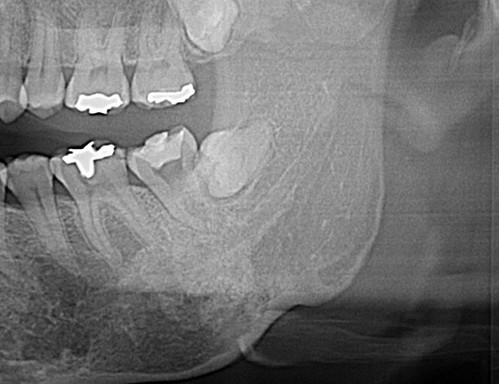

사랑니를 뽑고 오라는데 무서워서 수면치료를 받고 싶으시다고

매복 사랑니 발치는 환자에게 가해지는 자극이 세기때문에 중간에 힘을 주면 약간의 반응을 보이기도 하고 나중에 기억을 못하시기는 하지만 불편해하기도 한다.